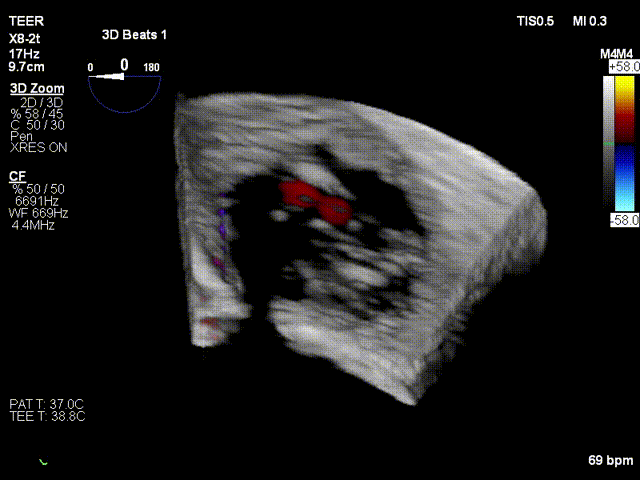

术前超声

术后超声